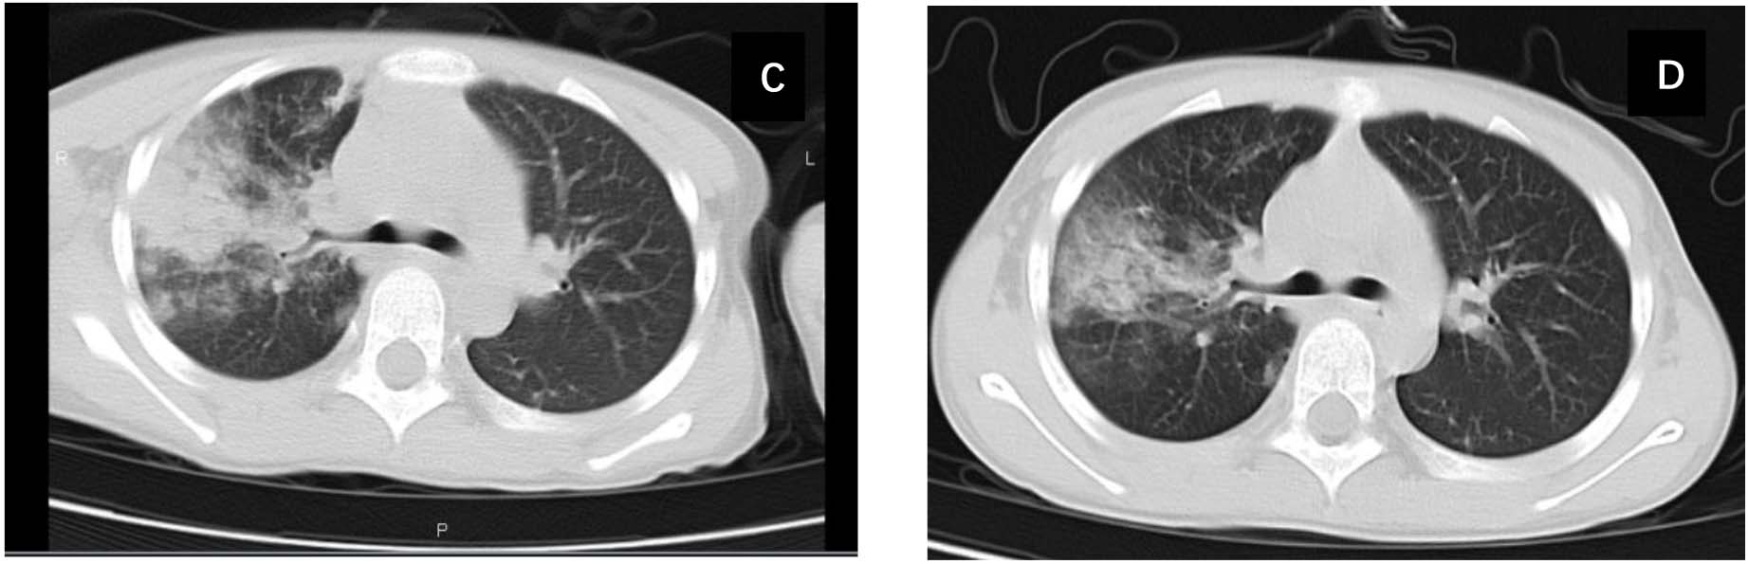

CT评分举例如下:图1图2显示两个患儿入院时的肺部CT表现及接受大致相同治疗方案10~14天后,复查的胸部CT表现及CT评分。

Figure 1. Chest CT images and CT scoring criteria for MPP in an 8-year-old female pediatric patient

1. 8岁女性患儿,MPP肺部CT检查图像及CT评分标准

图1(A)所示,入院时肺部CT示右肺上叶约20%的两个小区域的肺实变(CT评分,2 + 1)。如图1(B) 所示,治疗7天后复查肺CT示右肺上叶实变面积增大,超过50%,不足75% (CT评分,4 + 1)。